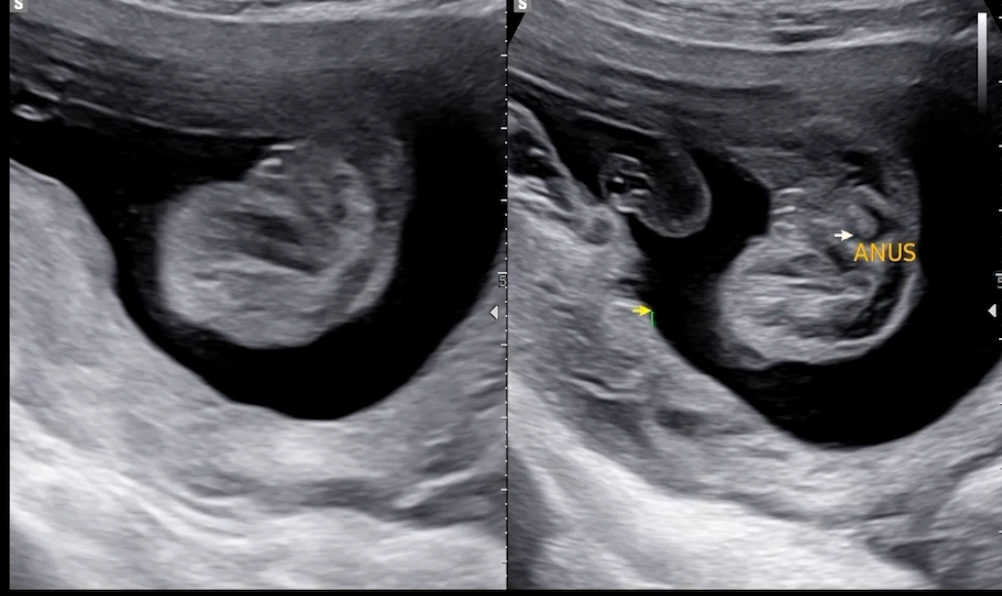

선생님이 말해주시기 전까지는 몰랐던 항문..! 잘 열려있는지 확인했구요. 원래도 성별은 알고 있었지만, 이 때 성별을 한 번 더 말해주셔요. 공주님~~ ❤️